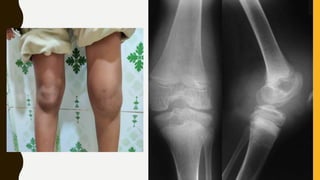

Joint Contracture in the Left Elbow in a patient

With Hemophilia A.

The Elbow joint is a target joint in this patient.